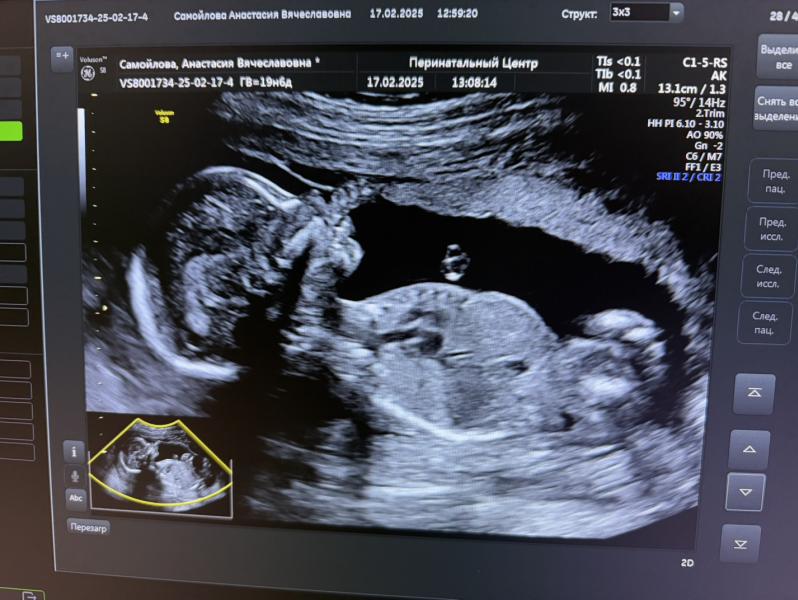

Наша малышка 😍

Прошли 2-й скрининг, как всегда на отлично!))

Вес примерно 330г., ноги за головой🙈 гимнастка) 🤸♀️

оба узиста (была сегодня платно в клинике и бесплатно в перинатальном) отметили очень красивый нос 🙈